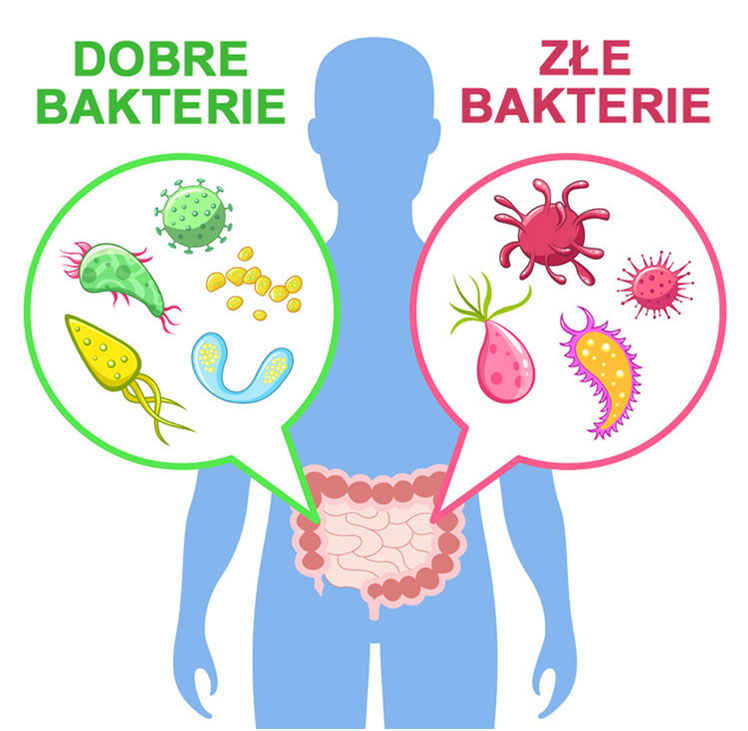

Śmierć zaczyna się w jelitach

Gdyby nie one, zakończyłbyś życie z powodu nawet drobnej infekcji. Ale obrona twojego organizmu przed śmiertelnymi patogenami to nie jedyne ich zadanie.

Wyobraź sobie, że właśnie zjadłeś posiłek bogaty w białka, witaminy i minerały. Aby z tego posiłku pozyskać życiodajne substancje odżywcze, potrzebujesz kilku bilionów dobrych bakterii. Ci probiotyczni pracownicy dosłownie wydobywają cenne składniki odżywcze z masy strawionego jedzenia. Następnie pozyskane przez nie składniki odżywcze transportowane są przez śluzówkę jelita do twojego krwioobiegu, który to z kolei transportuje je do 40 bilionów fabryk w postaci komórek na terenie całego twojego organizmu.

Ale jeśli w twoich jelitach jest niewiele dobrych bakterii, cała masa cennych składników odżywczych, które właśnie zjadłeś, wyląduje zwyczajnie w muszli klozetowej, a 40 000 000 000 000 komórek na terenie twojego organizmu zostanie skazanych na zagłodzenie, a ty niestety razem z nimi. Zjawisko to nazywa się głodem komórkowym i w krótkim czasie może doprowadzić do skrajnego wyniszczenia i śmierci twojego organizmu.

W konsekwencji poziom dobrych bakterii spada do drastycznego minimum. A potrzeba ich biliony, aby utrzymać system odpornościowy w pełnej gotowości. Dziecko ze zniszczonym układem odpornościowym nie jest w stanie obronić się nawet przed niewielką infekcją. A każda niedoleczona infekcja to ciągnące się latami powikłania, które w życiu dorosłym wybuchną dużo poważniejszymi schorzeniami.

Czyli nasza odporność znajduje się w jelitach. IIe jest w tym prawdy?

Dobre bakterie są bardzo pilne, uczestniczą w złożonym procesie rozpoznawania patogenów. Za każdym razem jak na teren twojego organizmu wkracza wrogi patogen w postaci bakterii czy wirusa, twój układ odpornościowy uczy się go rozpoznawać i uruchamia produkcję specyficznych przeciwciał. Gdy ponowny raz taki patogen wkroczy na teren twojego organizmu, zostanie on natychmiast rozpoznany, a produkcja przeciwciał błyskawicznie uruchomiona. Wyprodukowane przeciwciała łączą się z patogenami, i w konsekwencji patogen zostaje zneutralizowany i usunięty z organizmu. Infekcja zostaje zatrzymana, a ty często nawet nie zdajesz sobie sprawy w jakich opałach się znalazłeś.

Już wiesz, że jeśli złe bakterie skolonizują twoje jelita, praktycznie nie masz żadnych szans na przezwyciężenie jakiejkolwiek choroby.

Jeśli natomiast w twoich jelitach jest dużo dobrych bakterii, te złe zwyczajnie nie mają gdzie się podziać, i są zmuszone opuścić twój organizm.